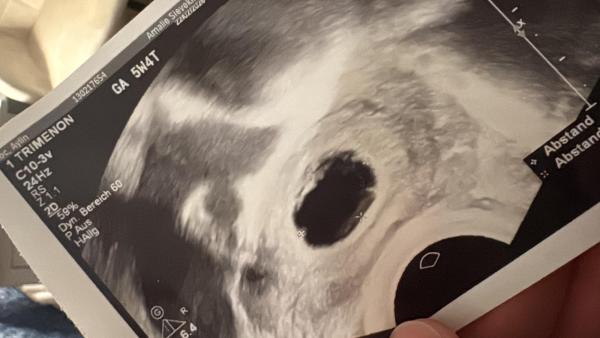

Ich war zur untersuchen wurde geschallt leider nur eine fruchthöhle zu sehen. Mein hcg 19.400  hatte das jemand auch und ist trzdem gut verlaufen ??

Bild zu 5+4 ssw nur fruchthöhle hcg relativ hoch - Schwanger - wer noch? Rund um die Schwangerschaft